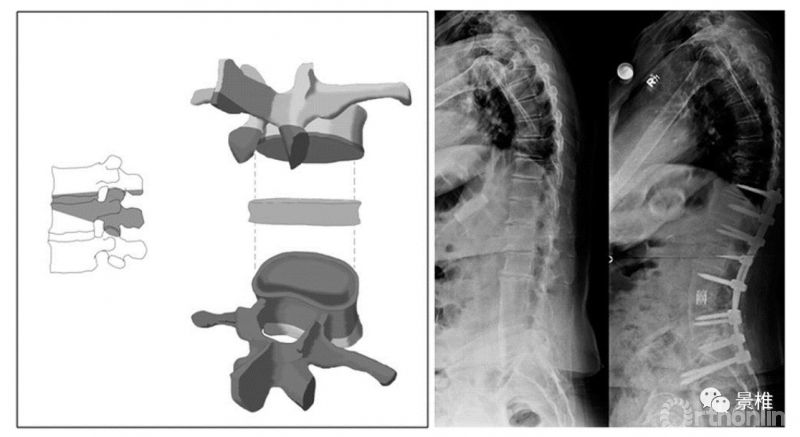

5级 VCR

5级,彻底拿掉一个椎体及上下间盘,在胸椎还包括同序列肋骨。一个椎体的叁柱全部切除了,所以也叫VCR(Vertebral Column Resection)。后凸矫形可达50º。

VCR简明图解:

VCR(vertebral column resection),椎体叁柱切除术。第一步,切除椎体后方结构。

如果在胸椎做VCR,还得把截骨椎两侧肋椎关节以及肋骨切除4-5cm,注意这一步胸膜不要被肋骨残端戳破。

椎间隙植入钛笼,硬膜囊上覆盖明胶海绵之类的保护下,把截除肋骨噼成条,做后方植骨。安装横联。